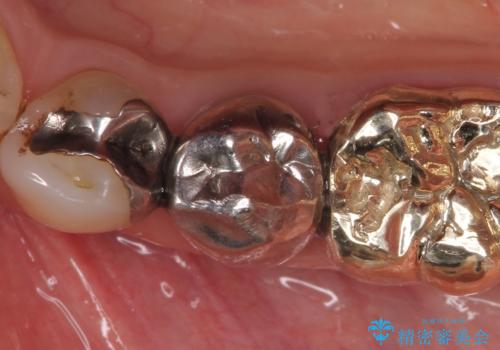

- 左下5番目の歯を根管治療からやり直したいといらっしゃった方の症例です。

再根管治療終了後、オールセラミッククラウンによる補綴を行いました。